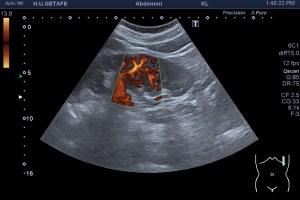

En este caso lo primero que tenemos que hacer es discernir entre si lo que tenemos en la pantalla es un tumor o es una hipertrofia de la Columna de Bertin, que por localización, pueden ser perfectamente ambas. Te recomiendo estudiar y documentar perfectamente la ecoarquitectura y una vez que hayas visto bien todo, pongas el doppler color y el modo angio con un objetivo. El objetivo es ver si la lesión está «rechazando vasos», es decir si los vasos se abren no siguiendo la normal vascularización de un riñón. Pasa a las imágenes 4 y 5…

Le hemos puesto la caja de color y los vasos nos son rechazados, esto nos va a tranquilizar, lo vamos a documentar muy bien, si estamos solos y en el documento que adjuntemos al radiólogo informaremos de este hallazgo para que él vea si es es necesario ampliar el estudio o no.

En este caso no fue necesario medir, claramente estábamos frente a una hipertrofia de una Columna de Bertin, variante de la normalidad típica de los estudios del riñón y que puede ser descubierta por varias técnicas de imagen.

La hipertrofia de la Columna de Bertin es isoecogénica con el parénquima renal. Hay que distinguirla de la duplicación del sistema y tumores renales isoecogénicos, y aquí reside también otra característica que tiene que ver con la semiología de la imagen, la isoecogenicidad, y la homogeneidad de la imagen.